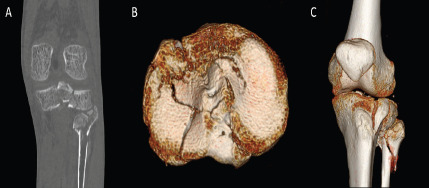

Methods: A retrospective analysis was conducted on 23 patients with peri-knee fractures, using both 2D and 3D-CT scans. Three radiologists classified distal femur, patella, and tibial plateau fractures according to Arbeitsgemeinschaft für Osteosynthesefragen/Orthopaedic Trauma Association (AO/OTA) and Schatzker systems. Reliability was measured using Cohen's kappa, with evaluations conducted at two separate intervals to assess intra- and inter-observer consistency.

Abstract Image